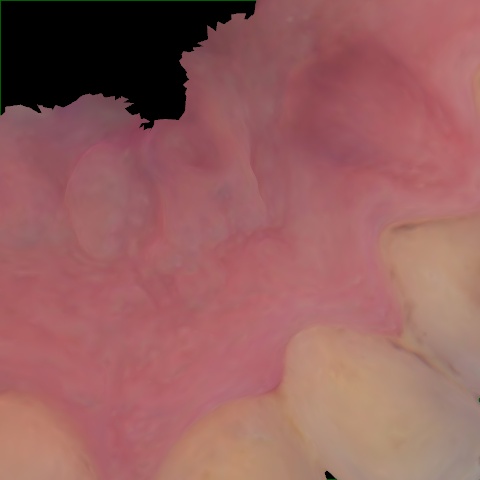

NHD39969

Annotated as "Good"

Original Image Rendering Image